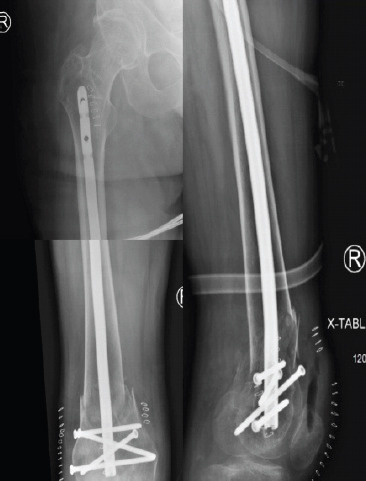

Case report: A 45-year-old male with T2 paraplegia presented with bilateral distal femoral shaft fractures following a motor vehicle accident. He underwent bilateral retrograde intramedullary nailing to preserve mobility and independence. Postoperatively, the patient developed a hypertrophic non-union on the right side with hardware migration, requiring revision with plate and screw fixation. Subsequently, he developed painful hardware on the right and severe heterotopic ossification on the left, significantly impacting his quality of life. Although hardware removal was recommended, the surgeries were never performed due to the patient's clinical course and eventual death from unrelated causes.